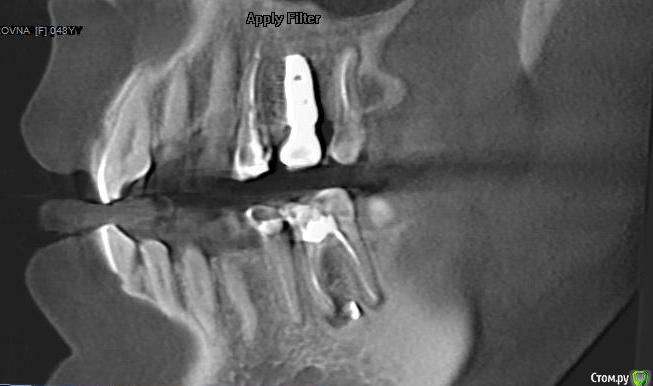

В феврале 2018 была проведена одномоментная имплантация системой Dentium верхней правой пятерки,  имплантат хорошо прижился, в сентябре протезирование винтовой металлокерамической коронкой. Коронка изначально была не идеальна, не были учтены мои пожелания пока ходила с временной, некоторые моменты пришлось корректировать уже во рту после установки. С самого начала я ее чувствовала как инородный предмет (2 импланта, которые стоят с 2008 года, я не чувствую вообще), но решили пока походить так, чтобы привыкнуть.

В ноябре 2018  поставили диагноз артроз и назначили хондопротекторы+гиалуроновая кислота+коллаген для восстановления хряща. Примерно через восемь месяцев приема препаратов на всей верхней и нижней челюсти появились наросты (экзостоз). Челюстно-лицевой хирург сказал, что удалять пока смысла нет, наросты дискомфорта не причиняют, визуально не видны и лучше не лезть (осень 2019) . Я обратилась к тому же врачу-стоматологу с жалобой на дискомфорт в области имплантата.  Чувство  инородного предмета во рту усилилось, ощущение онемевшего "замороженного" зуба даже при чистке щеткой.  На снимке доктор  проблем с имплантатом  не обнаружил. Решили снять и подкорректировать коронку, в результате при вскрытии пломбы повредили головку винта, открутить не смогли. Промучились час, запломбировали обратно и отпустили. Как вариант доктор предложил срезать коронку, но я не решилась на такие радикальные действия. С марта 2020 года появились ноющие боли в верхней правой половине челюсти и головные боли, отдающие в правую часть лба. Я грешила на имплантат, десна вокруг коронки была розовая, но болезненная с внешней и внутренней стороны. Поехала к тому же врачу, сделали снимок, с имплантатом  все хорошо, но доктор сказал, что воспалилась соседняя четверка (стояла большая пломба), хотя на надкусывания и постукивания зуб не реагировал.  Вскрыли пломбу, зуб пролечили, каналы запломбировали (июнь 2020), головные боли ушли. Четверку подготовили к покрытию коронкой.

На сегодняшний день  имеется следующее: постоянные тянущие ощущения в области 4-го зуба и имплантата, легкое реагирование на горячее/холодное, болезненная десна вокруг коронки. Доктор настаивает на покрытии 4 зуба коронкой, говорит, что реакция на горячее/холодное пройдет.

post-3819-0-90305200-1595925032_thumb.jpg

post-3819-0-99302800-1595925046_thumb.jpg

ссылка на КТ (Пикассо)